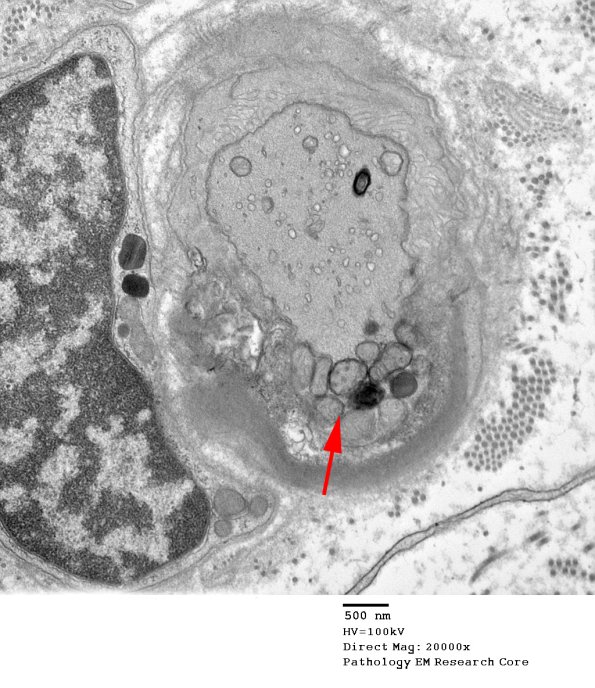

An asymmetric section shows scattered subcellular organelles on one side of the node (arrow) and microvilli on the other. (electron micrograph)